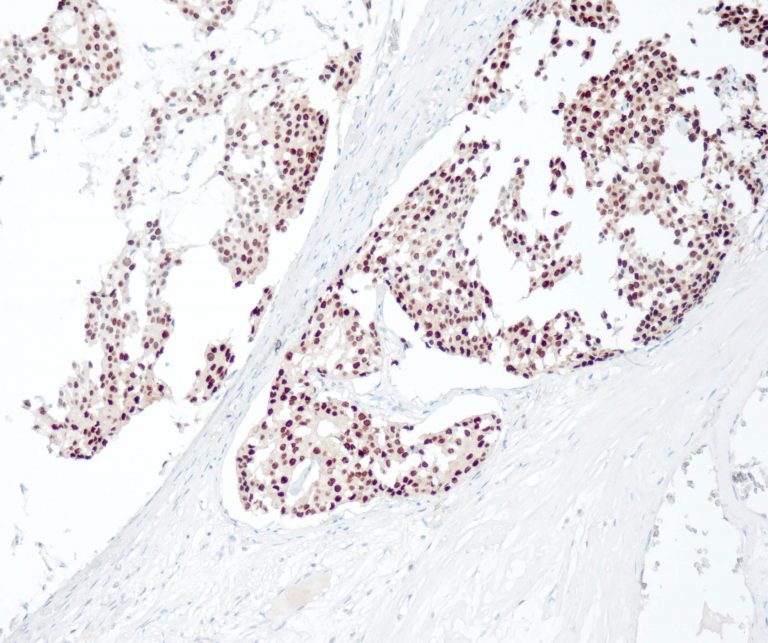

Vascular Pathology

Gastrointestinal (GI) Pathology

General Marker

Breast Pathology

Endocrine Pathology

Gynecological Pathology

Neuropathology

Infection Markers

Lung Pathology

Urinary Tract Pathology

Transplantation Pathology

Soft Tissue Pathology

Hematopathology